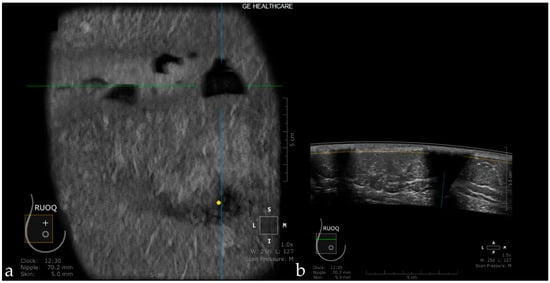

Skip Artifact

When the transducer quickly slides over a firm and superficial lesion (cyst, fibroadenoma), it creates a linear artifact, which is observed in the coronal plane and sagittal plane. It appears as a horizontal line located superior to the lesion [44] (Figure 5).

Figure 5. The case of a bulging cyst visible on both coronal (a) and axial planes (b) at 2.30 o’clock, 25.6 mm from the nipple (yellow dot). Due to the superficial location of the lesion, the transducer slides over its edge producing the skip artifact seen on the coronal plane (white dotted arrow).